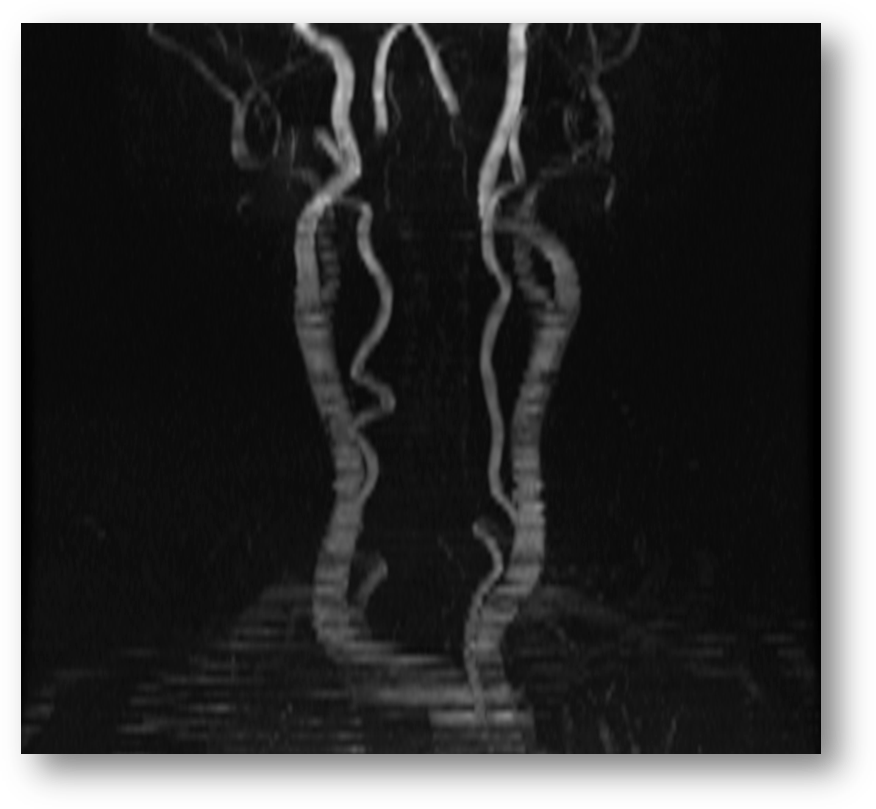

Refer to caption

Figure 8: 2D time-of-flight fast spoiled gradient echo sequence (FSPGR) image of the carotids.

MRA is a set of magnetic resonance-based techniques for imaging the circulatory system. Figures (9) and (10) show MRA images of the Circle-of-Willis. MRA techniques can be broadly categorized into flow-dependent and flow-independent groups. The flow-dependent methods derive contrast from the motion of blood in vasculature relative to the static state of surrounding tissue [33]. Two currently well-known and used examples of flow dependent methods are: (i) Phase contrast MRA, (PC MRA) [34, 37, 91] and (ii) Time-of-Flight MRA (TOF MRA). The TOF MRA images can be acquired in either two dimensional (2D TOF) or three dimensional (3D TOF) formats. Figure (8) shows a 2D TOF fast spoiled gradient echo sequence (FSGR) image of the carotids, and Figure (7) shows a an axial section of a 3D TOF image of the carotids. PC MRA exploits differences in spin phase of moving blood relative to static surrounding tissue, while TOF MRA exploits the difference in excitation pulse (B1subscript𝐵1B_{1}) exposure of flowing blood relative to static surrounding tissue. This difference occurs because flowing blood spends less time in the field of exposure, and as a result is less spin-saturated then the surrounding tissue. This decreased spin-saturation translates into higher intensity signals on spin-echo sequences.